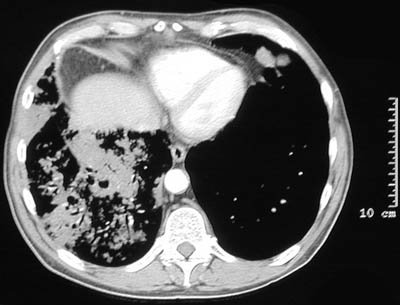

The chest CT scans in lung window above and bone window below demonstrate a very extensive bronchioloalveolar carcinoma involving most of the right lung. The tumor appears as large areas of consolidation resembling a pneumonia.